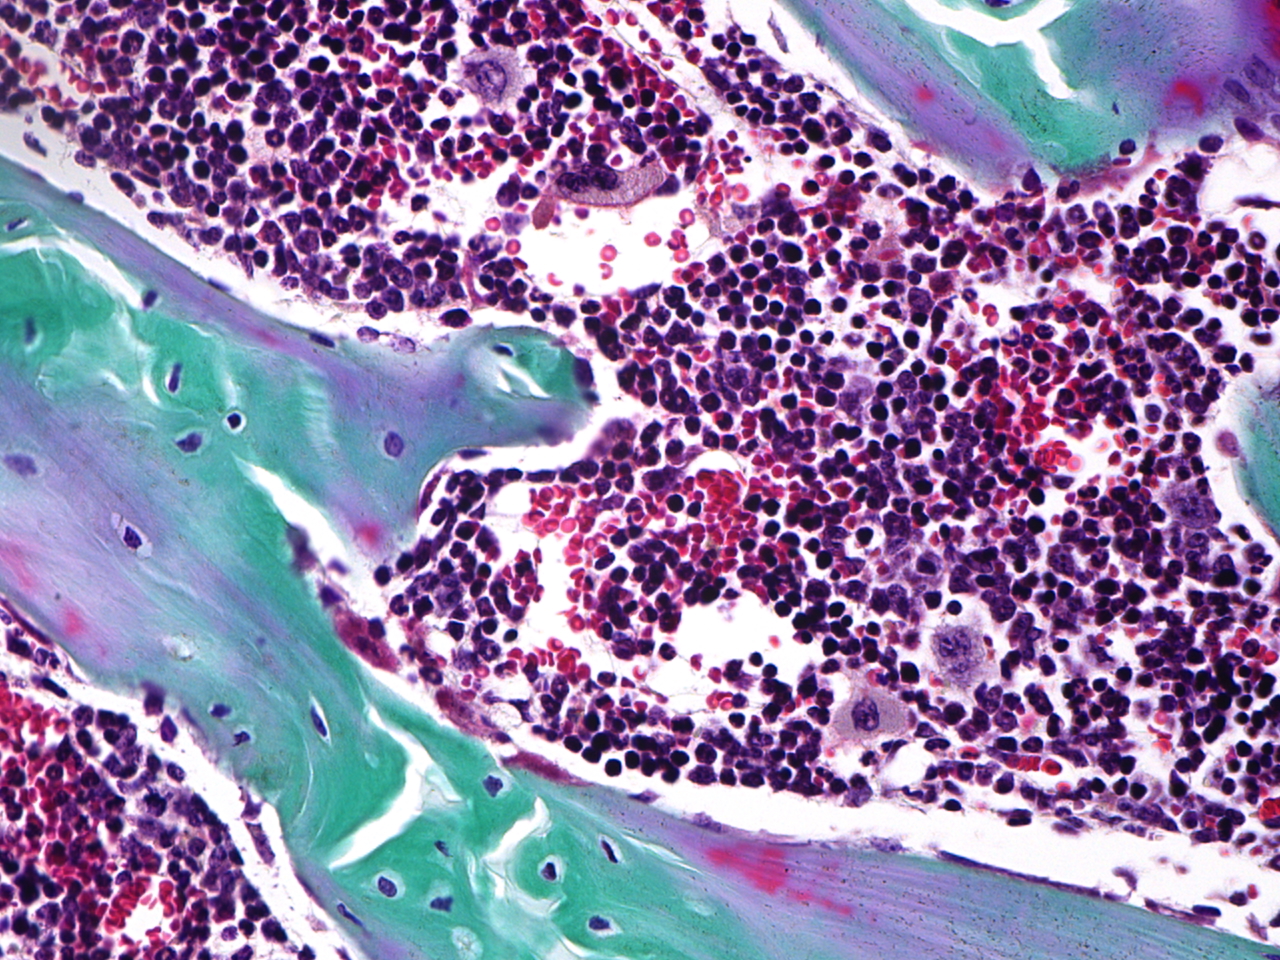

The MD Anderson Bone Histomorphometry Core Laboratory provides histomorphometric analyses of non-decalcified bone specimens. Bone specimens are processed for histology and can be stained for static and dynamic histomorphometric analyses (Osteomeasure or the Bioquant Osteo II system). The core can provides slides, data, training

Research Histology Core Lab: Bone Processing, Embedding and Sectioning

Bone Histomorphometry Core: Staining and Analysis